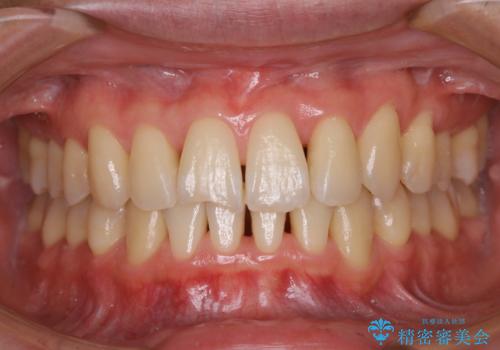

- 前歯をきれいにしたいとのことで来院されました。歯科医院でのクリーニングは半年ぶりでしたが、今回は前歯をメインにクリーニング希望だったためPMTCの30分コースを行いました。

今回は、前歯メイン希望とのことでしたが、歯石やプラークが薄い付着だったため、30分コースの中で全体的クリーニングが行えました。